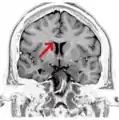

Coronal T2 (grey scale inverted) MRI of the brain at the level of the caudate nuclei emphasizing corpus callosum- Tractography of corpus callosum